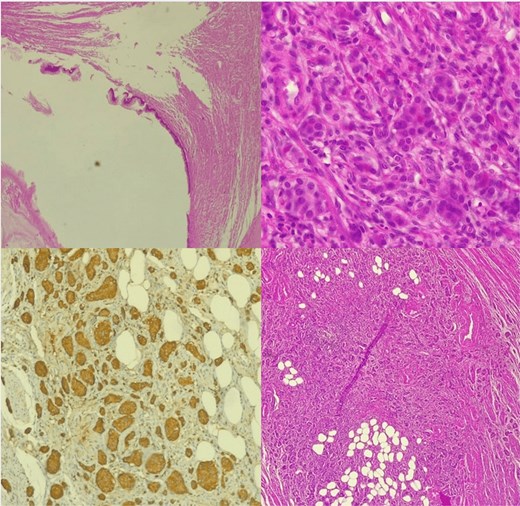

Histopathological analysis confirmed a NET of the appendix associated with an appendiceal mucocele, with clear appendiceal margins. Immunohistochemical analysis showed positivity for anti-chromogranin, anti-synaptophysin, and anti-pan cytokeratin antibodies, with a Ki67 proliferation index of 1% (Fig. 3).

Histological image of NET of the appendix associated with an appendiceal mucocele.

They are classified into three grades according to morphological differentiation and mitotic labeling index ki-67.

Grade 1 A well-differentiated tumor or a low-grade tumor with low mitotic activity, mitotic count ˂2/2mm2, ki-67 < 2% and a proliferation rate that resembles a normal cell.

Grade 2 intermediate tumors, or moderately differentiated tumors, share characteristics of grades 1 and 3 with moderate activity, mitotic count 2_20/2 mm2 and ki-67 3%–20%.

Grade 3 poorly differentiated high-grading tumors have a high rate of mitotic activity and proliferation mitotic count ˃20/2 mm2, ki-67 > 20% .